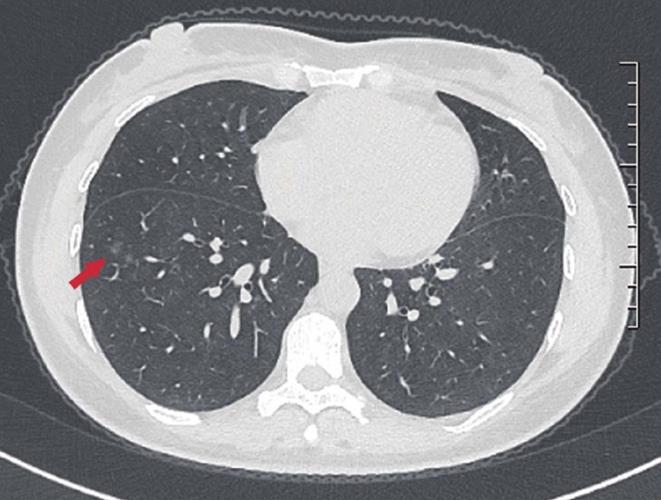

对于临床上首次发现的肺小结节,部分结节难以确定良恶性,在随访过程中有些患者的肺小结节被确诊为恶性结节,也就是肺癌。有些人一两个月就被确诊了,有些患者在首次发现肺小结节一两年后才被诊断为肺癌,而有些患者肺小结节多年没有变化最终被确诊为良性病变。其实,临床上首次发现肺小结节时,临床医生常根据患者的临床表现、胸部影像资料将患者肺小结节分类为高危、中危或低危结节并进行管理。很明显,高风险结节最终被发现为肺癌的时间较短。

肺小结节发展为恶性病变的时间不仅与患者肺部小结节的大小、结节在肺叶的位置、形状、钙化、边缘特征、生长速度等有关;还需要考虑患者本身的潜在风险因素,包括患者的年龄(55~74岁)、长期吸烟史(大于30年或戒烟小于15年)、既往有肺结核病史或长期肺部慢性炎症患者、既往的胸外恶性肿瘤病史、肿瘤家族史、接触石棉或放射性元素史等等。